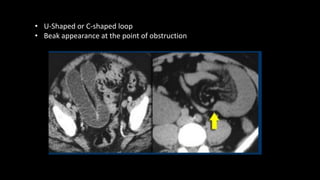

 Closed loop obstruction

• Two points in the segment of bowel is

obstructed

• When blood supply is compromised its

called strangulation

• CT is the imaging of choice

• A U-shaped loop of bowel is seen with a

transition point at either end.

• In severe cases, gas may be seen within the

bowel wall and within the portal venous

system

• U-Shaped or C-shaped loop

• Beak appearance at the point of obstruction